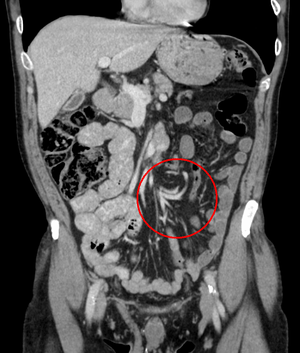

After taking a thorough history, the diagnosis of colonic volvulus is usually easily included in the differential diagnosis. Abdominal plain x-rays are commonly confirmatory for a volvulus, especially if a "bent inner tube" sign or a "coffee bean" sign are seen. These refer to the shape of the air filled closed loop of colon which forms the volvulus. Should the diagnosis be in doubt, a barium enema may be used to demonstrate a "bird's beak" at the point where the segment of proximal bowel and distal bowel rotate to form the volvulus. This area shows an acute and sharp tapering and looks like a bird's beak. If a perforation is suspected, barium should not be used due to its potentially lethal effects when distributed throughout the free infraperitoneal cavity. Gastrografin, which is safer, can be substituted for barium.

Diverticulitis is a common condition with different presentations. Although diverticulitis may be the source of a colonic obstruction, it more commonly causes an ileus, which appears to be a colonic obstruction.[11] Endoscopic means can be used to secure a diagnosis although this may cause a perforation of the inflamed diverticular area. CT scanning is the more common method to diagnose diverticulitis. The scan will show mesenteric stranding in the involved segment of edematous colon which is usually in the sigmoid region. Micro perforations with free air may be seen.